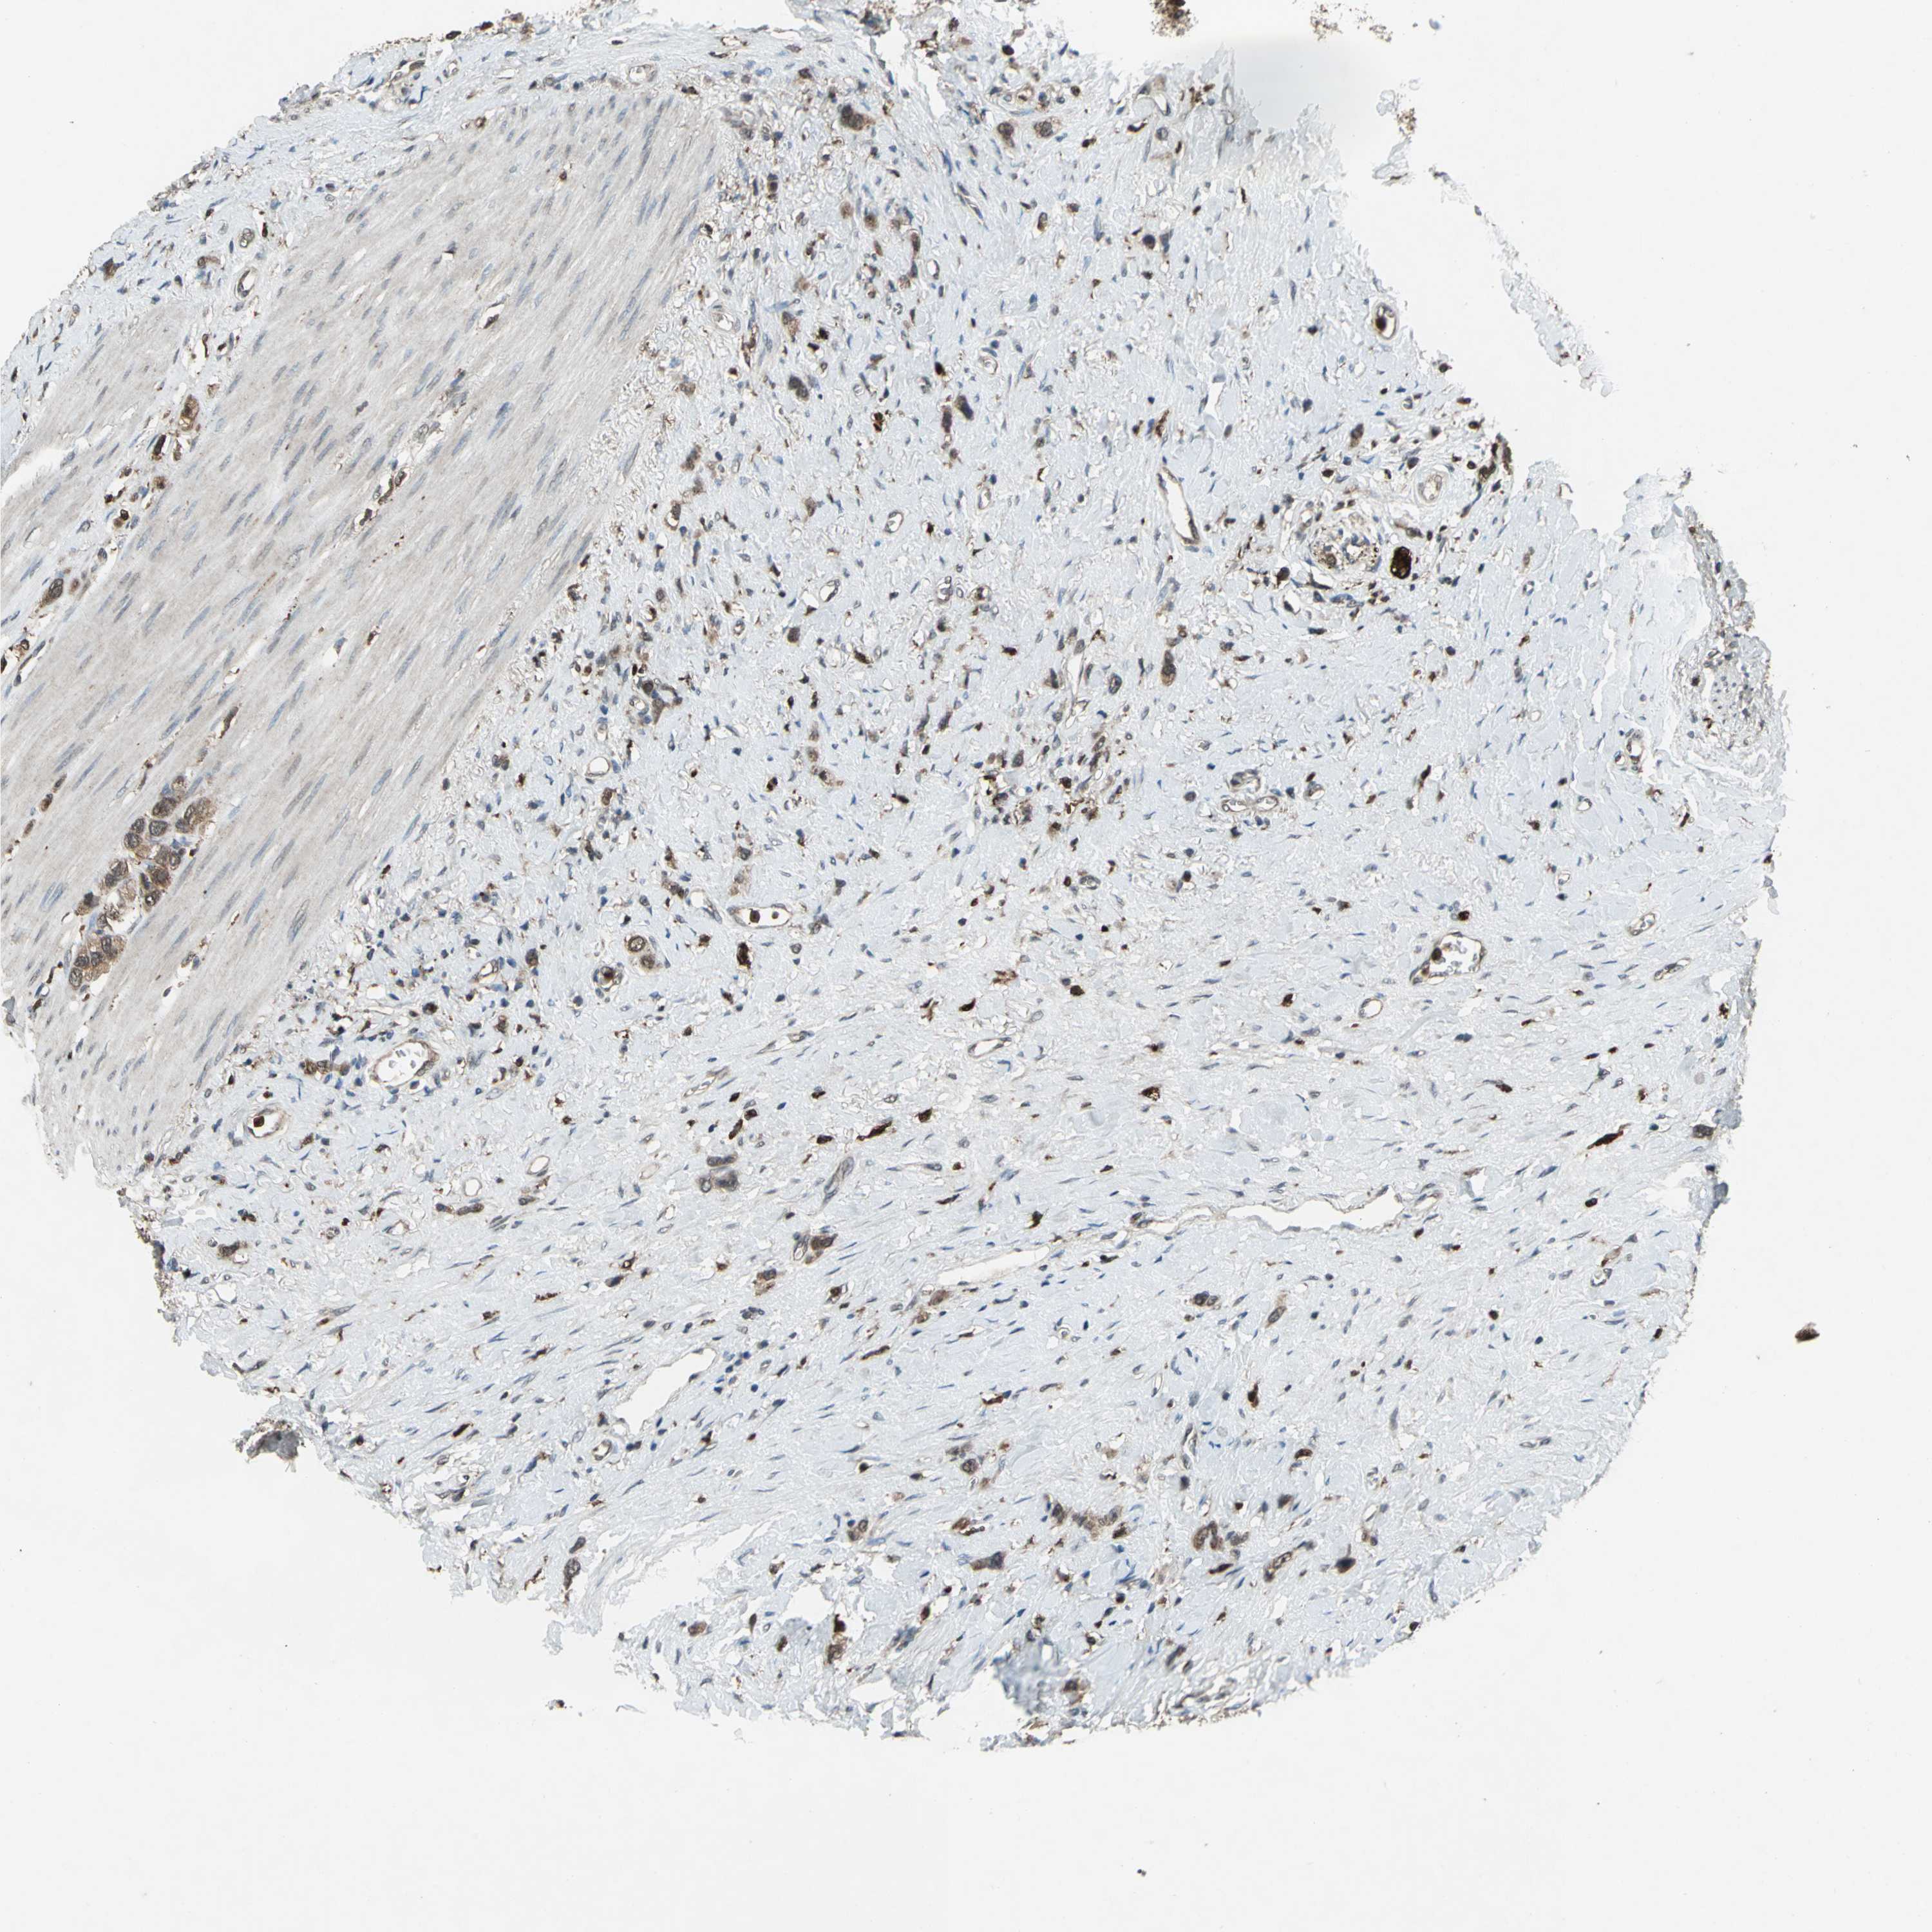

STOMACH CANCER - Protein expressioni

A mouse-over function shows sample information and annotation data. Click on an image to view it in a full screen mode. Samples can be filtered based on level of antibody staining by selecting one or several of the following categories: high, medium, low and not detected. The assay and annotation is described here.

Note that samples used for immunohistochemistry by the Human Protein Atlas do not correspond to samples in the TCGA dataset.

Antibody stainingi

Antibody staining in the annotated cell types in the current human tissue is reported as not detected, low, medium, or high, based on conventional immunohistochemistry profiling in selected tissues. This score is based on the combination of the staining intensity and fraction of stained cells.

Each image is clickable and will lead to virtual microscopy that enables deeper exploration of all samples and also displays staining intensity scores, fraction scores and subcellular localization as well as patient and tissue information for each sample.

Antibody HPA049074

Antibody HPA054496

Antibody CAB006853

Antibody CAB015948

Staining

High

Medium

Low

Not detected

Intensity

Strong

Moderate

Weak

Negative

Quantity

>75%

75%-25%

<25%

None

Location

Nuclear

Cytoplasmic/membranous

Cytoplasmic/membranous,nuclear

Adenocarcinoma, NOS

Adenocarcinoma, High grade